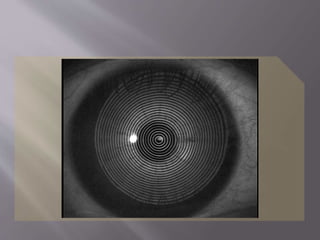

 Queratoscópios

 Sistema de Placido (disco o cono). ██

 Placido con topografía arquimétrica. ██ ██